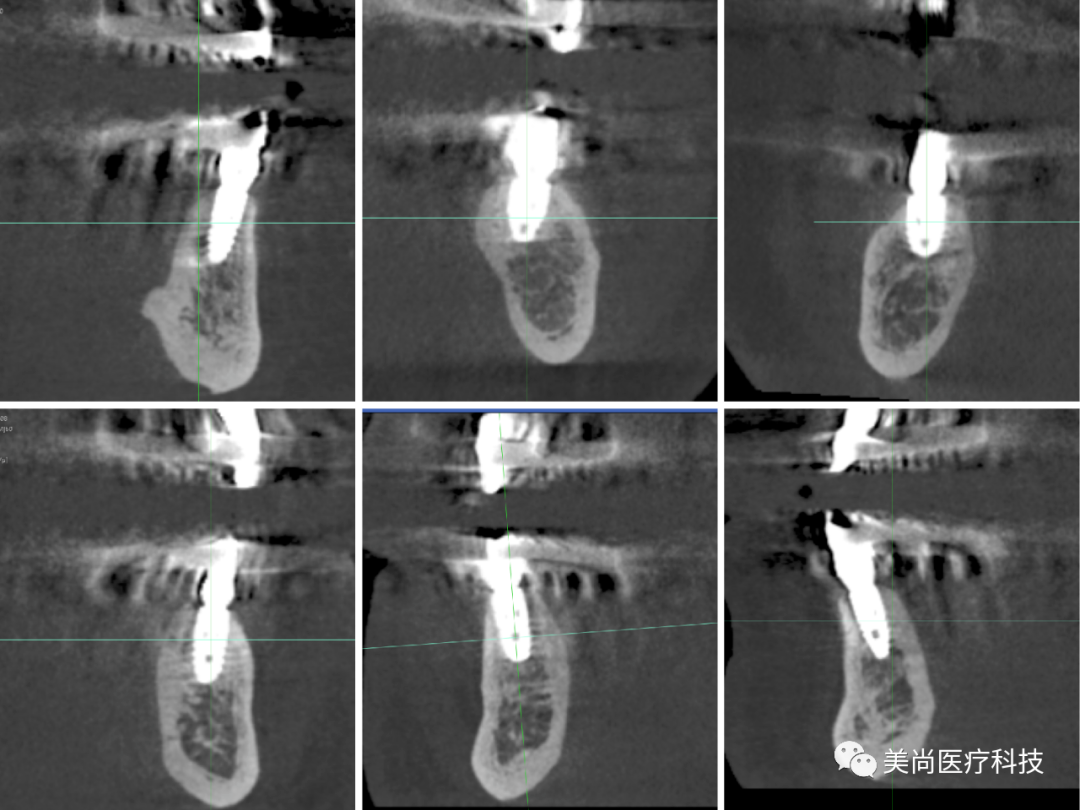

术前X-ray